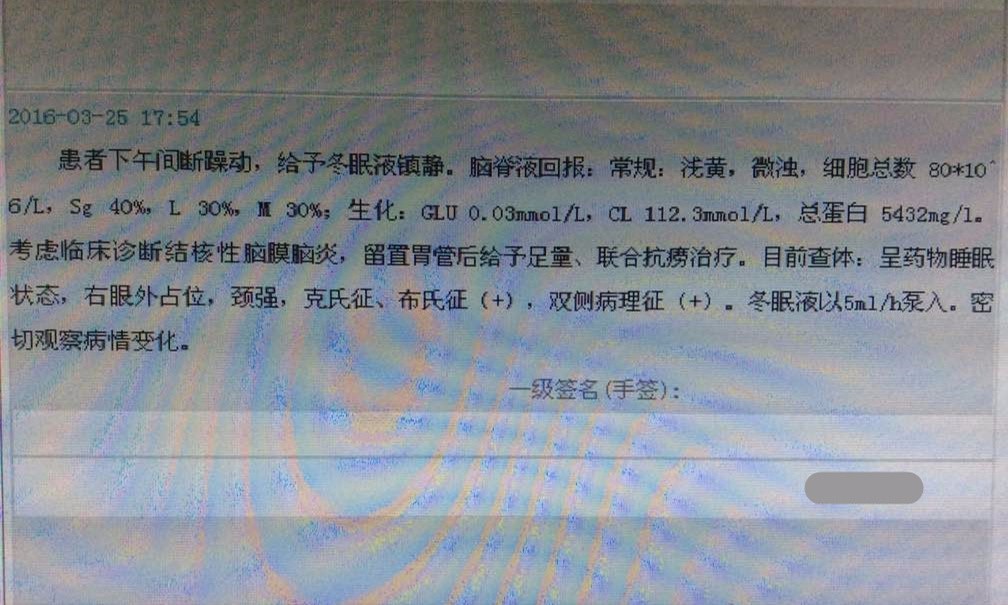

2016-3-25腰穿压力>300mmH2O,细胞计数80×106/L,脑脊液蛋白5.432g/L,葡萄糖0.03mmol/L,氯化物112.3mmol/L,脑脊液IgG601mg/L。脑脊液墨汁染色(-),抗酸染色(-),间皮细胞30%,单核细胞30%,多核细胞40%。

1.青壮年,急性起病,以头痛、癫痫、脑膜炎体征为主,同意中枢神经系统感染的诊断。

2.脑脊液改变不除外结核感染,但头MRI改变非典型结核影像。左额叶病灶似以脑外为主,波及对侧及额窦,不排除慢性感染病灶急性破入蛛网膜下腔。左额叶病灶与脑脊液信号等信号,DWI也为低信号,说明非急性病变。